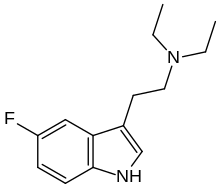

| 5-Fluoro-DET | artificial | 5-F | CH2CH3 | CH2CH3 | 5-fluoro-N,N-diethyltryptamine | |